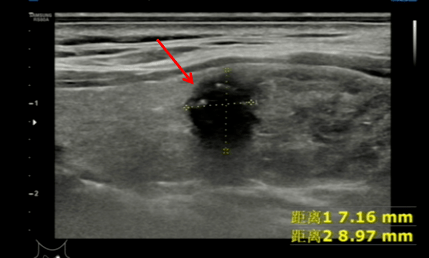

结节为低回声结节,边界欠清,纵横比大于1。(TI-RADS分类:4a类)